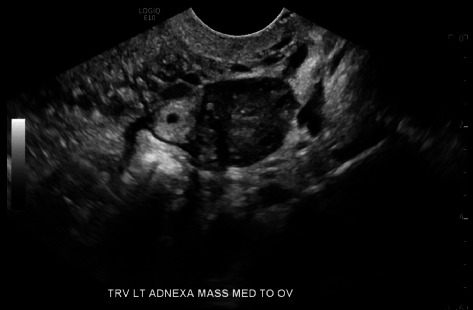

单侧输卵管双胎妊娠的发病率为1/20,000-1/250,000,约有100例报道。在接受药物治疗的六例病例中,有四例取得了成功。一名 24 岁女性因阴道出血和腹部绞痛到急诊科就诊。她的血流动力学稳定,没有急腹症迹象。实验室评估显示她怀孕了,血清中的β-人绒毛膜促性腺激素(b-hCG)为798 mIU/mL。经阴道超声检查(TVUS)发现左侧单侧输卵管妊娠,并伴有卵黄囊。患者选择了以体表面积(BSA)为基础的肌肉注射(IM)甲氨蝶呤(MTX)药物治疗。第4天,患者返回急诊室;她的b-hCG为727 mIU/mL。TVUS 显示双胎左侧输卵管妊娠,卵黄囊和胎儿极无心活动。患者选择继续接受药物治疗,并服用了第二剂基于 BSA 的 IM MTX。第 6 天,患者因腹痛和直肠痛返回急诊室。她的血流动力学稳定,没有急腹症迹象。她的 b-hCG 为 533 mIU/mL。TVUS 显示左侧输卵管持续性双胎妊娠,其中一胎孕龄 5 周,另一胎孕龄 6 周,无破裂迹象。患者继续接受连续的 b-hCG 检查。在首次服用 MTX 31 天后,她的 b-hCG 为

The incidence of unilateral tubal twin pregnancy is 1/20,000-1/250,000 with about 100 reported cases. Four of the six cases that were medically managed were successful. A 24-year-old female presented to the emergency department (ED) with vaginal bleeding and abdominal cramping. She was hemodynamically stable without signs of an acute abdomen. Laboratory evaluation revealed she was pregnant with a serum beta-human chorionic gonadotropin (b-hCG) of 798 mIU/mL. Transvaginal ultrasound (TVUS) revealed a single left tubal pregnancy with a yolk sac. The patient elected medical management with body surface area (BSA)-based intramuscular (IM) methotrexate (MTX). On Day 4, the patient returned to the ED; her b-hCG was 727 mIU/mL. TVUS revealed twin left tubal pregnancies with yolk sacs and fetal poles without cardiac activity. The patient elected to continue medical management with a second dose of BSA-based IM MTX. On Day 6, the patient returned to the ED with abdominal and rectal pain. She was hemodynamically stable without signs of an acute abdomen. Her b-hCG was 533 mIU/mL. TVUS showed persistent twin left tubal pregnancies-one at 5 weeks gestational age and the other at 6 weeks gestational age-without evidence of rupture. The patient continued serial b-hCGs. Thirty-one days after the first dose of MTX, her b-hCG was < 1 mIU/mL. TVUS showed resolution of tubal pregnancies. The patient consented to the publication of this case report. This case documents the successful treatment of spontaneous, unilateral tubal twin pregnancies with two-step dosing of IM MTX.